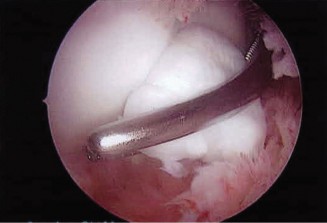

The correct answer is (A). When a chronic, retracted subscapularis tendon tear is present, the superolateral border of the tear can be identified by a comma-shaped ligamentous structure that exists at this border. This is composed of an avulsed superior glenohumeral ligament blending with the coracohumeral ligament and is called the comma sign (see Fig. 2–12).

_Figure 2–12_Comma sign, indicating the superior border of a chronic, retracted subscapularis tendon tear. G, glenoid; H, humerus; SSc, subscapularis; M, medial sling of biceps (comma); , junction of medial sling of biceps and subscapularis tendon. (Redrawn from Burkhart SS, Lo IKY. Arthroscopic rotator cuff repair. J Am Acad Orthop Surg. 2006;14(6):333–346.)